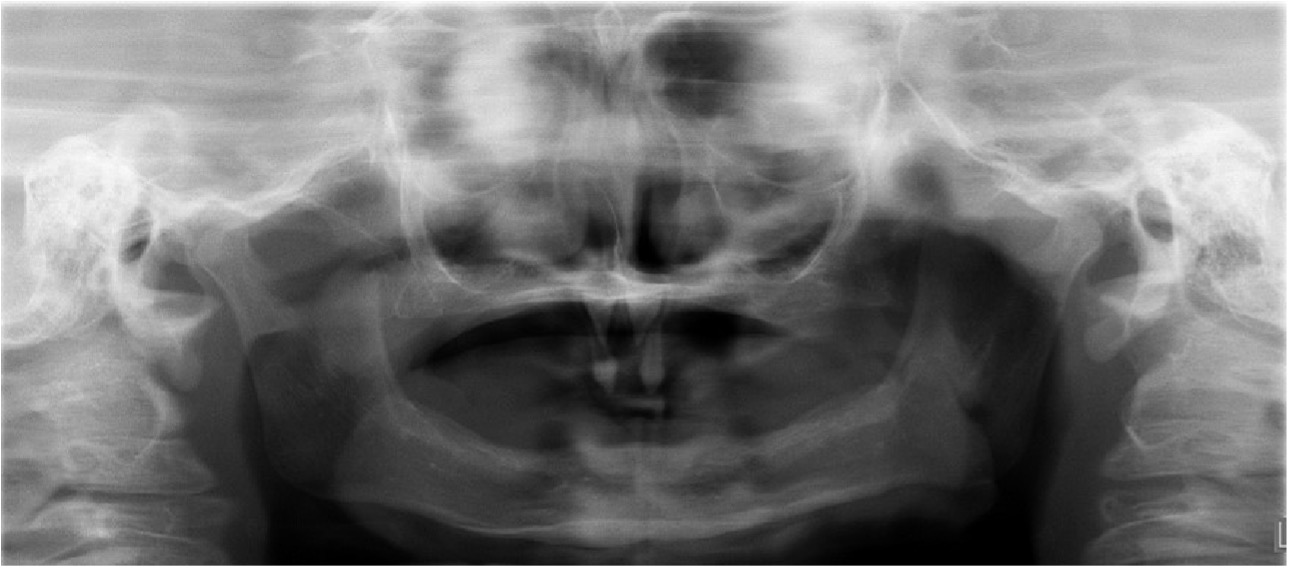

En el examen clínico intraoral se observa Anodoncia Parcial Verdadera con presencia únicamente de los dientes 52 y 62 de forma cónica, reborde alveolar atrófico y estrecho y disminución de la dimensión vertical (Figura 2). En la ortopantomografía se observa la ausencia de todos los gérmenes dentarios permanentes con excepción de los dientes 11 y 21 en forma cónica (Figura 3) (Tabla 1).

Figura 3: Radiografía panorámica.